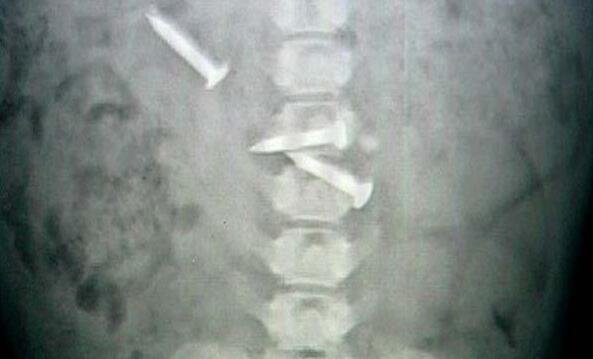

我立马就联想到这货肯定是吞了什么不该吞的东西了,于是赶紧送这货去了医院,果然,医生给狗狗做了手术之后,发现了一大堆乱七八糟的东西,其中有就有铁钉。

医生看了之后判断说狗狗吞下的时间还不长,要是等到发病之后再送来,还真心就危险了。真心是佩服我家狗狗了,真的是什么都敢吃啊! |